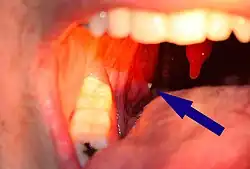

Le terme se retrouve aussi dans une formation « normale » (non pathologique) associée aux amygdales. Seule cette version prend le nom de « tonsillolithe » (des mots « tonsille », synonyme d'amygdale, et « lithe », qui veut dire pierre).[source insuffisante]

Pouvant être en cause dans la mauvaise haleine, le caséum a l’apparence de minuscules grains, susceptibles de se calcifier, de s’enkyster (voir kyste) ou de se ramollir après imprégnation hydrique.